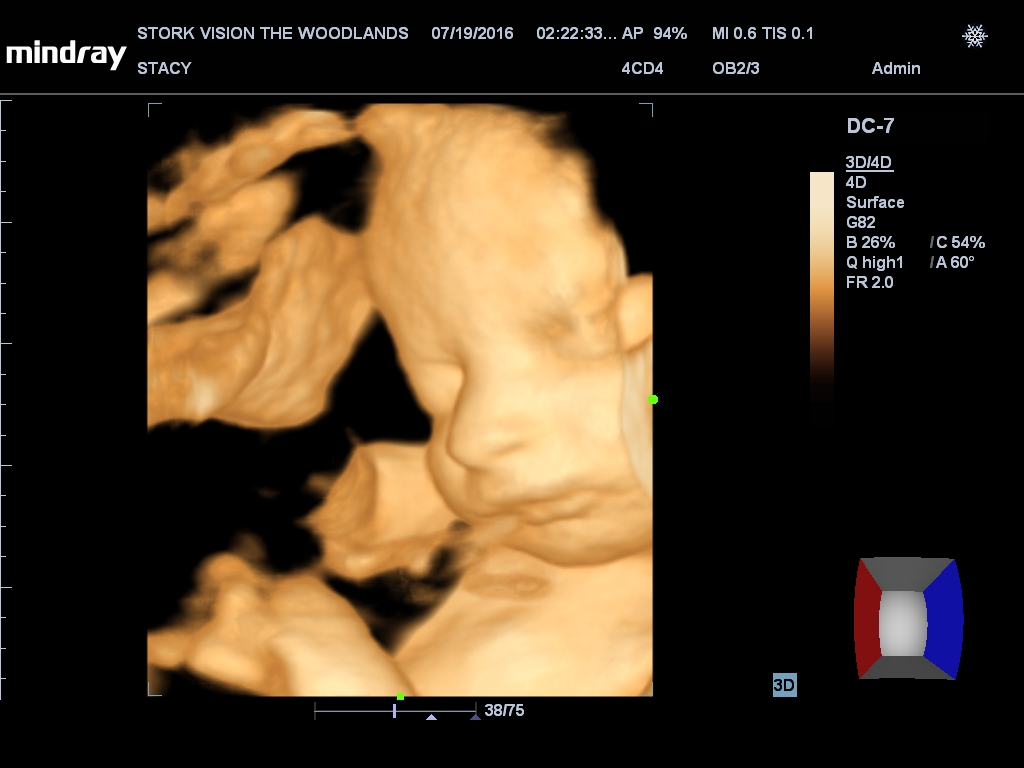

Gender: GIRL!

Best moment the week: Seeing Juliette on the 3D/4D ultrasound. So amazing!